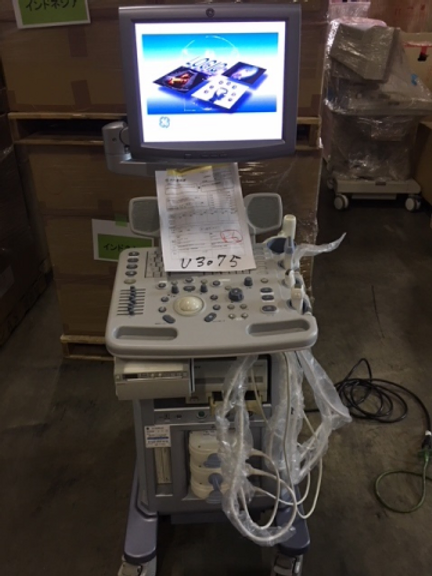

Elevate Your Diagnostic Experience with the LOGIQ P5 Ultrasound Scanner

Introduction: Experience cutting-edge imaging technology at an affordable price with the LOGIQ P5 Ultrasound Scanner. Compact, ergonomic, and packed with high-end features, this ultrasound device redefines diagnostic excellence without breaking the bank.

Unrivaled Imaging Capability: From gynaecology/obstetrics to urology, cardiology, and paediatrics, the LOGIQ P5 delivers exceptional 3D/4D imaging across a range of medical specialties. With its advanced features, it stands as the most powerful system in its price range, offering unmatched diagnostic precision and clarity.

Feature-Rich Performance: Enjoy access to premium features typically found on more expensive devices, including CrossXBeam composite imaging, cardiac imaging, and speckle reduction. The LOGIQ P5 sets a new standard for affordability without compromising on performance.

Enhanced Functionality: Equipped with a 15-inch TFT LCD monitor and a flexible monitor arm, the LOGIQ P5 ensures optimal viewing comfort and convenience during procedures. With a spacious 50 GB hard disk for image storage and directional power Doppler imaging, it meets the demands of modern healthcare settings.

Effortless Optimization: Streamline your workflow with automatic tissue optimization, coded harmonic imaging, and high pulse repetition rate capabilities. The LOGIQ P5 is designed to enhance efficiency and accuracy, empowering healthcare professionals to focus on patient care.

Key Features:

- Compact and ergonomic design for enhanced usability

- Versatile imaging capabilities across multiple medical specialties

- Premium features including CrossXBeam composite imaging and cardiac imaging

- 15-inch TFT LCD monitor with flexible monitor arm for optimal viewing

- 50 GB hard disk for ample image storage

- Directional power Doppler imaging for detailed vascular assessments

- Automatic tissue optimization and coded harmonic imaging for enhanced image quality

- High pulse repetition rate for improved diagnostic accuracy

Experience the future of ultrasound imaging with the LOGIQ P5. Elevate your diagnostic capabilities and redefine patient care with its unparalleled performance and affordability.